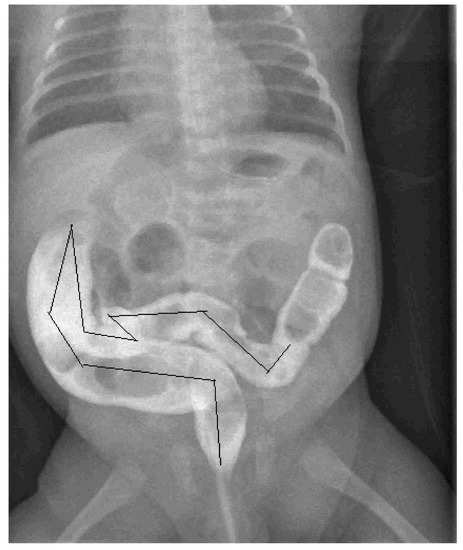

To obtain better results, three blinded operators (two pediatric surgeons and a pediatrician) independently measured the size of the colon on the same radiographic image, evaluating the diameters of the rectum, sigmoid colon, descending colon, transverse colon and ascending colon, then measuring the length of the sigmoid colon (Figure 1). To standardize the results as much as possible and avoid weight and age-related variations, the ratios between the measured diameters of the various intestinal segments and the length of the sigmoid colon with the width of the body of the second lumbar vertebra (L2) were calculated. This same procedure has already been performed and reported by other authors as well as in our previous study of children with severe constipation older than 1 year [6]. The calculated ratios were compared with those reported as normal in one-year-old children in the literature [7]. The distribution of the data was verified by the Shapiro–Wilk test on median values with an interquartile range. In comparison, the study data used as a control was obtained with the Mann–Whitney U test. The level of the p-value indicating significance was set at 0.05. The Social Science Statistical Package (SPSS) v.22 (IBM, Armonk, NY, USA) was used to perform statistical analyzes.

Figure 1. Image of CE of 2-months-old infant: the black line shows the rectosigmoid length.